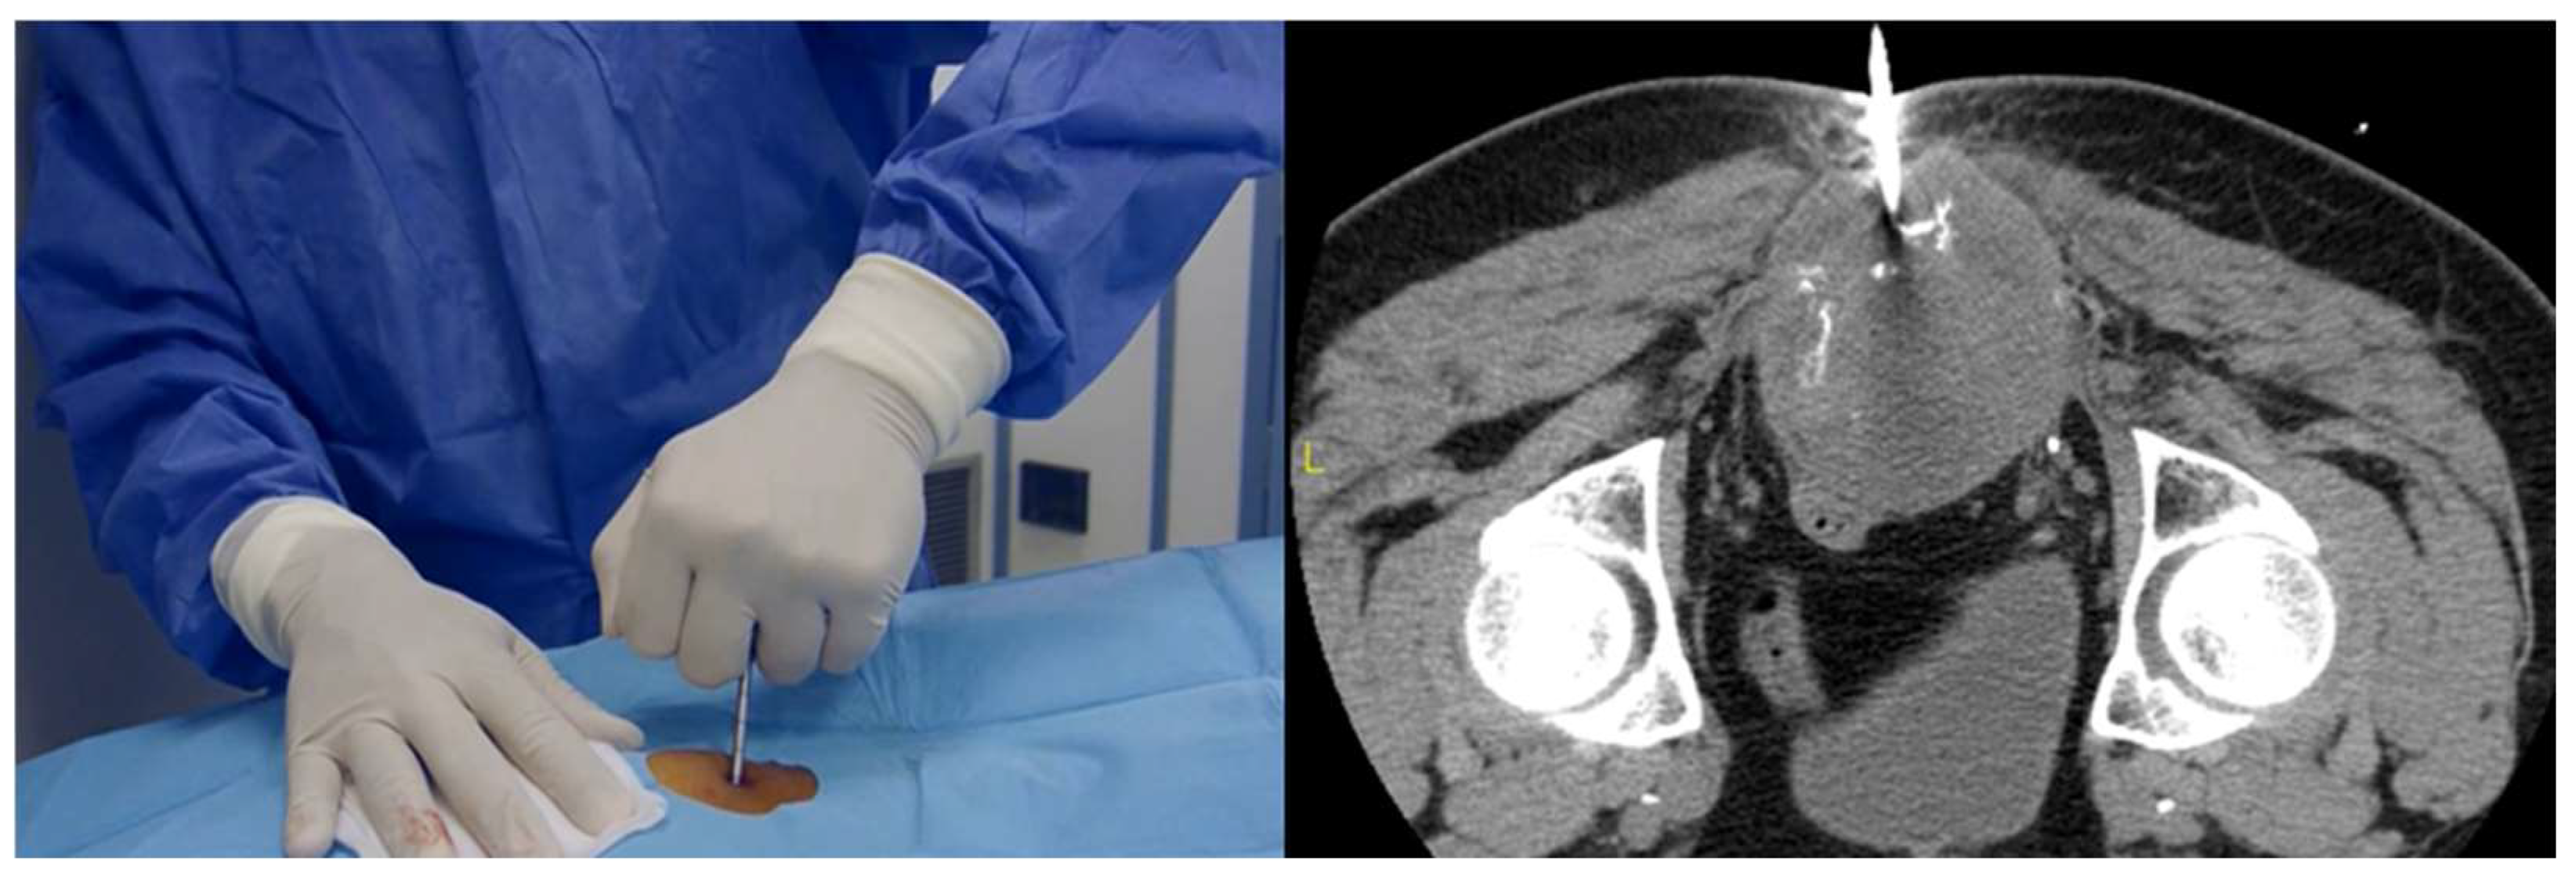

2.2. Core-Needle Biopsy

| Closed biopsy | The gold standard, especially if guided. Minimally invasive, high accuracy (no difference with open biopsy), cost effective, rare complications (<11%). |